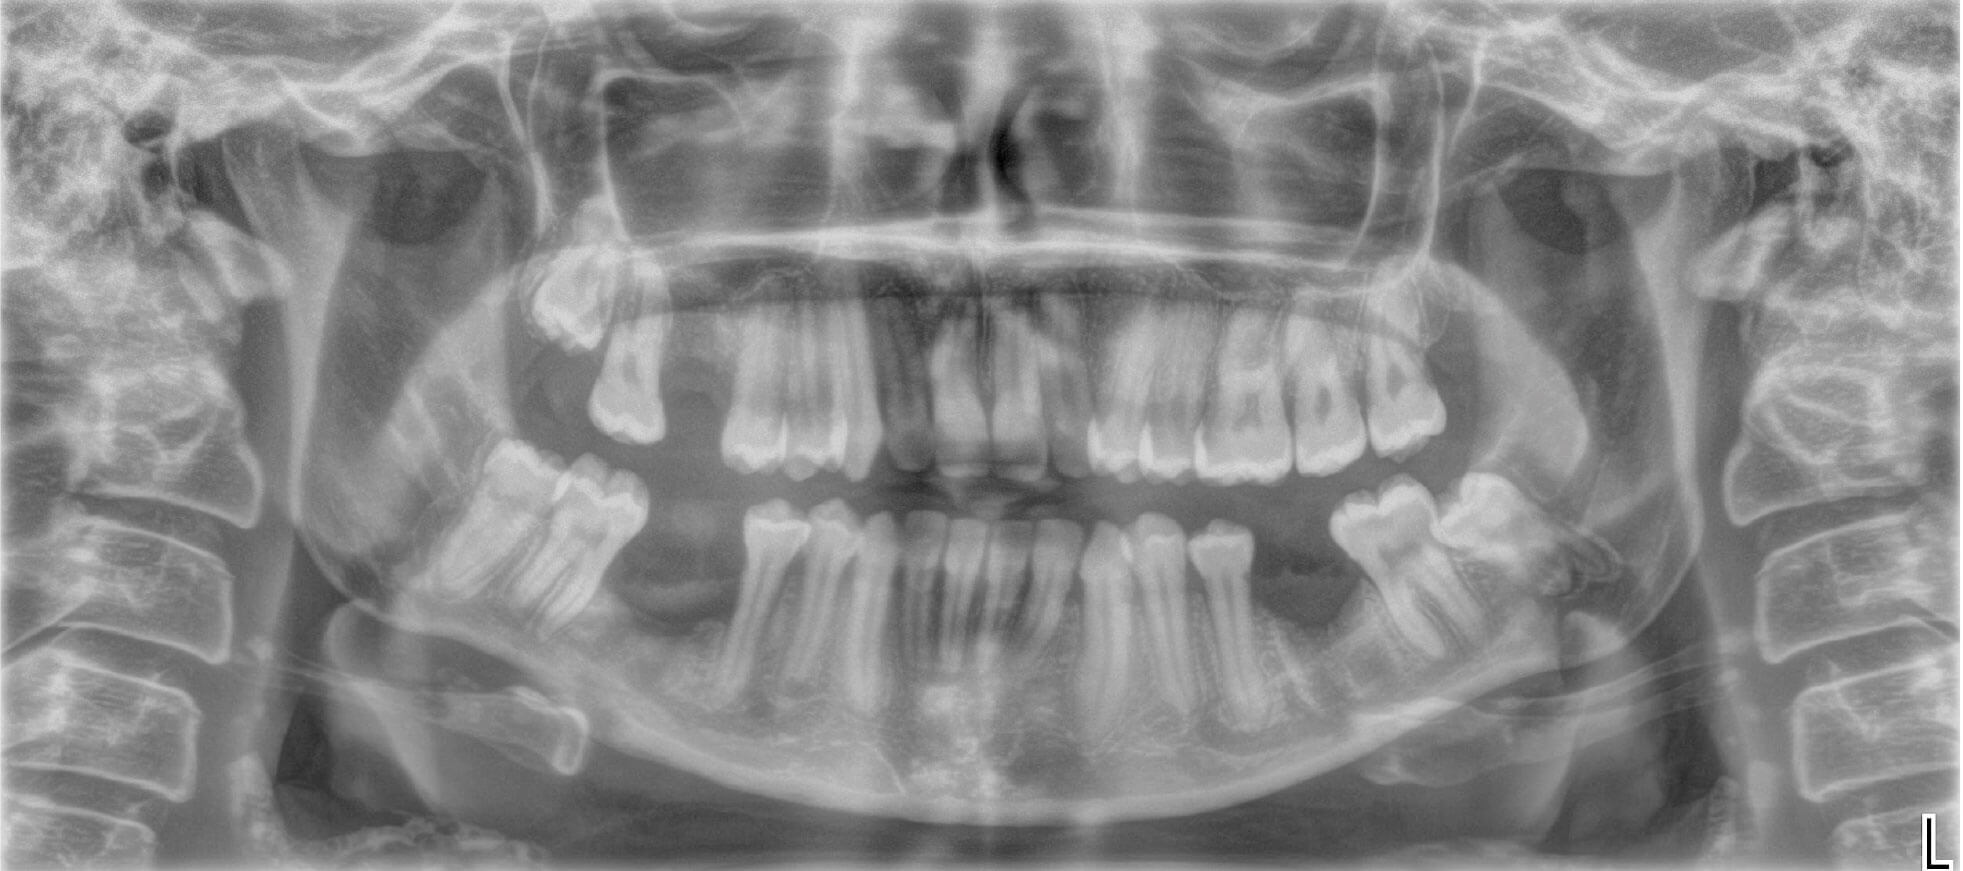

Figure 5: OPG showing external fixation in place.

The patient was then reviewed in one week’s time and an OPG was taken at this appointment (Figures 5). At this appointment, the patient reported minimal pain. On examination, the external fixation was stable, with evidence of intraoral healing.The patient was then reviewed four and six weeks post ex-fix placement. No issues were identified and good mucosal healing with no inflammation or infection was apparent. At the six-week review, the mucosa appeared well healed and the patient’s numbness had almost completely resolved. The OPG showed good bony infill.